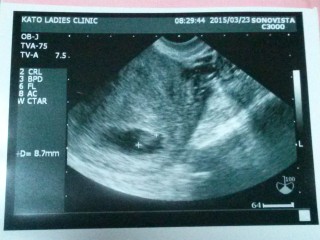

仮分娩予約のために産院へ。 よく動いてますよー、と言われました。カルテには正常妊娠と記録。 CRLは5.2mmでまだルティナス膣錠の力を借りていますが、先生からは小さいとも言われていないので、きっと大丈夫。